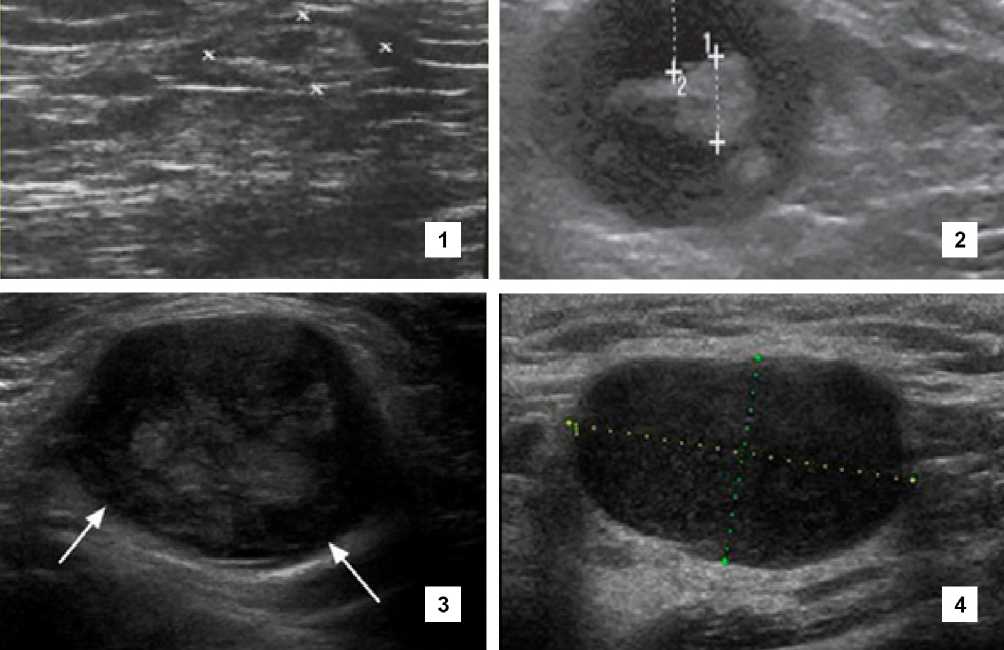

Из признаков, характерных для метастатического поражения лимфатического узла, были выявлены потеря овальной формы и округление, снижение соотношения длинника

к поперечнику, увеличение продольного диаметра более 10 мм (> 10 мм), наличие таких контурных изменений, как нечеткость, неровность границ; спаянность с окружающими тканями; отсутствие четкой капсулы (рис. 1).

Р и с . 1 . Ультразвуковая картина лимфатических узлов; 1 – аксиллярный лимфатический узел в норме; 2 – округлая форма лимфоузла при метастатическом поражении; 3 – лимфоузел с нарушением дифференцировки; 4 – лимфоузел без прослеживания дифференцировки

F i g . 1 . Ultrasound picture of lymph nodes; 1 – normal axillary lymph node; 2 – rounded shape of lymph node with metastatic lesion; 3 – lymph node with impaired differentiation; 4 – lymph node without differentiation

Источник : здесь и далее в статье рисунки были получены в ходе исследования в программе APLIO MX Source : hereinafter in the article, the drawings were obtained during research in the APLIO MX program.

Опишем обнаруженные варианты (табл. 2). Первый включает изменение отношения поперечного и продольного размеров (длинной и короткой осей) лимфатического узла, которое становится менее 1,5. Лимфатический узел имеет округлую форму, гипо- или анэхогенную структуру. Чем ближе форма к округлой, тем выше вероятность метастатического поражения лимфоузла. При этом отмечается расширение кортикального слоя, «размытие» капсулы. Типичным для метастаза в лимфоузел признаком является нарушение внутренней архитектуры: исчезновение дифференцировки на корковый и мозговой слои; неоднородность эхоструктуры (ан-, гипо- и гиперэхогенные включения).